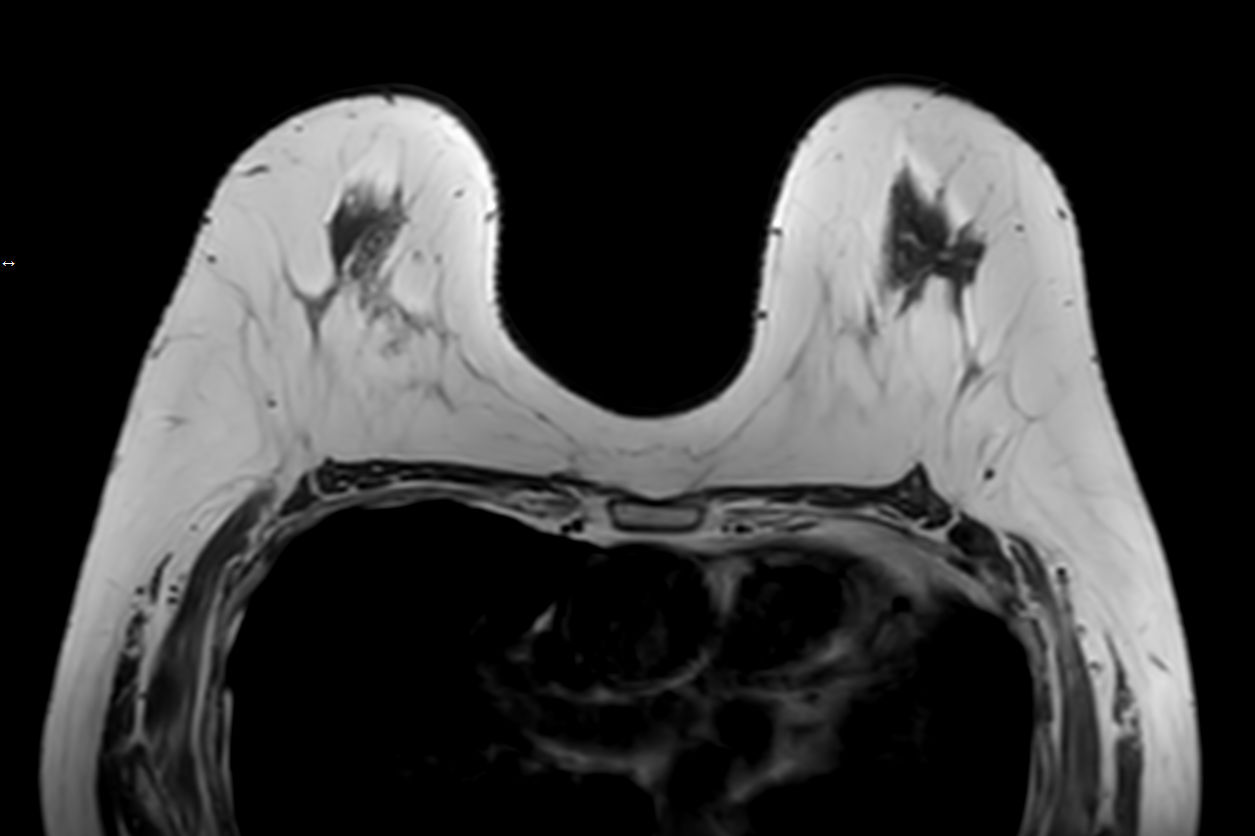

T1w TSECompressed SENSE